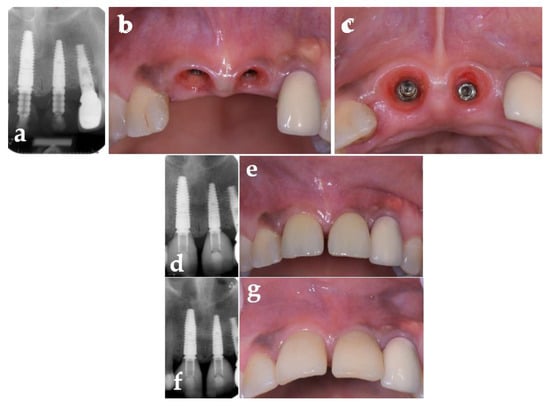

| Marginal Bone Level Site 11 (2D) [mm] | ||||

|---|---|---|---|---|

| Site 11 | Site 21 | |||

| Mesial | Distal | Mesial | Distal | |

| Post-OP | +2 | +2 | +1 | 0 |

| 1 year | +2 | +2 | +1 | 0 |

| 2 years | +1.5 | +1.5 | +1 | 0 |

| 3 years | +1.5 | +1.5 | +1 | 0 |